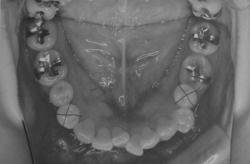

17日でこんな感じに変わってきました。思ってたより動きが早いわぁ。

こんなもんなのかな、それともデーモンシステムのお陰?

今回ワイヤーが少しぶっとくなって1箇所バネが入りました。まだひとつブラケットが付けられない歯があるんだよね~。痛いけど早く動いてほしいなぁ。

右側の飛び出た歯が少し移動したので、抜歯根が狭くなってきました

2006/10/27撮影 (抜歯前の写真です。×印は抜歯済)

2007/02/06撮影

あと、写真ではわかりませんが、ちゃんと生えきってなかった右の奥歯が真っ直ぐに生えてきました。そして奥歯が両方いっぺんに噛み合わせられるようになってきました~~~

上から3番目の写真は、歯医者さんで器具を使ってびろ~んと上下左右にひっぱりながら撮ってもらいました。このときって、もう絶対おもろい顔してると思うのよね~。